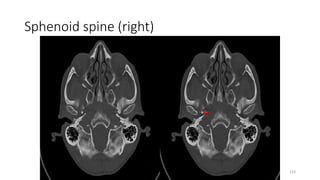

Sphenoid spine (right)

133